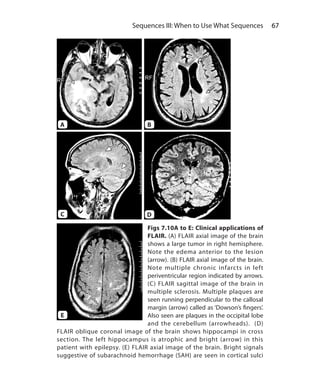

Chapter 7.  Sequences III: When to Use What Sequences	58

T2-Weighted Sequences	 61